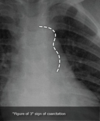

Q

Dato clave del patrón de consolidación alveolar